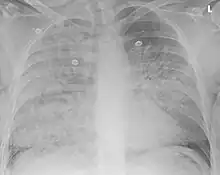

Aspiration pneumonia in a ventilated person with a central line and nasogastric tube

Severe aspiration pneumonia

Aspiration pneumonia is typically diagnosed by a combination of clinical circumstances (people with risk factors for aspiration) and radiologic findings (an infiltrate in the proper location).[2] A chest x-ray is typically performed in cases where any pneumonia is suspected, including aspiration pneumonia.[17] Findings on chest x-ray supportive of aspiration pneumonia include localized consolidation depending on the patient's position when the aspiration occurred.[18] For example, people that are supine when they aspirate often develop consolidation in the right lower lobe of the lung.[18] Sputum cultures are not used for diagnosing aspiration pneumonia because of the high risk of contamination.[19] Clinical symptoms may also increase suspicion of aspiration pneumonia, including new difficulty breathing and fever after an aspiration event.[6] Likewise, physical exam findings such as altered breath sounds heard in the affected lung fields may also be suggestive of aspiration pneumonia.[6] Some cases of aspiration pneumonia are caused by aspiration of food particles or other particulate substances like pill fragments; these can be diagnosed by pathologists on lung biopsy specimens.[20]